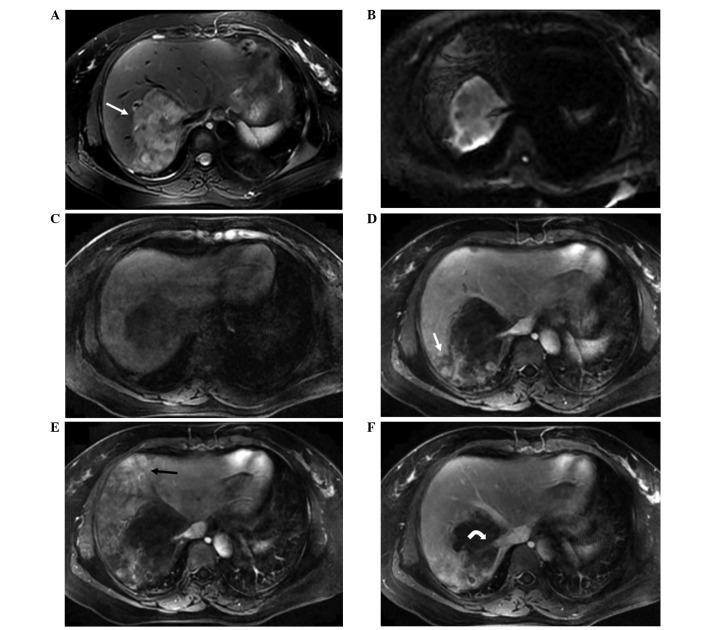

To investigate the typical magnetic resonance imaging (MRI) and computed tomography (CT) features of hepatic epithelioid hemangioendothelioma (HEH), the CT and MRI findings of 14 histopathologically confirmed cases of HEH were retrospectively analyzed. Non-contrast and dynamic contrast-enhanced scans were conducted in all cases. A total of 229 lesions were detected in the 14 cases. All cases were classified as one of three types: (i) Solitary nodular type (1 case, 7%); (ii) multifocal nodular type (11 cases, 79%); or (iii) diffuse type (2 cases, 14%). The diameter of the lesions ranged from 5 to 105 mm. For the first two types (solitary and multifocal nodular types), the CT findings included low density lesions with clear margins on non-contrast scans, centripetal enhancement in arterial phase, and homogeneous enhancement in the portal venous and delay phases. The findings of non-contrast MRI scans for these two types included low signal intensity on T1-weighted images, heterogeneous high signal intensity on T2-weighted images, and heterogeneous high signal intensity on diffusion-weighted images. The lesions were predominantly located in submarginal areas. On contrast-enhanced MRI, the findings for the first two types included peripheral ring-like enhancement with a central low signal intensity ('black target-like' sign) and a central enhanced core surrounded by a low signal intensity halo ('white target-like' sign). The findings for the third HEH type (diffuse type) on CT and MRI scans included low density or heterogeneous signal intensity lesions involving regions of part or the whole liver, coalescent lesions ('strip-like' sign), and gradual enhancement along central vessels ('lollipop' sign). Collectively, these findings indicate that the 'white target-like' sign, 'black target-like' sign, 'lollipop' sign and 'strip-like' sign, in addition to capsular contraction and submarginal location, on CT and MRI imaging may have implications for the diagnosis of HEH. Furthermore, a variety of MRI sequences may provide additional information for the differential diagnosis of HEH.

为研究肝上皮样血管内皮瘤(HEH)的典型磁共振成像(MRI)及计算机断层扫描(CT)特征,对14例经组织病理学确诊的HEH患者的CT和MRI表现进行回顾性分析。所有病例均行平扫及动态增强扫描。14例患者共检出229个病灶。所有病例分为以下三种类型之一:(i)孤立结节型(1例,7%);(ii)多灶结节型(11例,79%);或(iii)弥漫型(2例,14%)。病灶直径5~105 mm。前两种类型(孤立结节型和多灶结节型),CT表现为平扫低密度病灶,边界清晰,动脉期向心性强化,门静脉期及延迟期均匀强化。这两种类型的MRI平扫表现为T1加权像低信号,T2加权像不均匀高信号,扩散加权像不均匀高信号。病灶主要位于边缘下区域。增强MRI表现为前两种类型有周边环形强化,中央低信号(“黑靶征”)及中央强化灶周围有低信号晕(“白靶征”)。第三种HEH类型(弥漫型)的CT和MRI表现为低密度或信号不均匀的病灶累及部分或整个肝脏区域,融合病灶(“条带征”),沿中央血管逐渐强化(“棒棒糖征”)。总体而言,这些表现表明CT和MRI成像上的“白靶征”“黑靶征”“棒棒糖征”及“条带征”,以及包膜皱缩和边缘下位置,可能对HEH的诊断有提示意义。此外,多种MRI序列可为HEH的鉴别诊断提供更多信息。